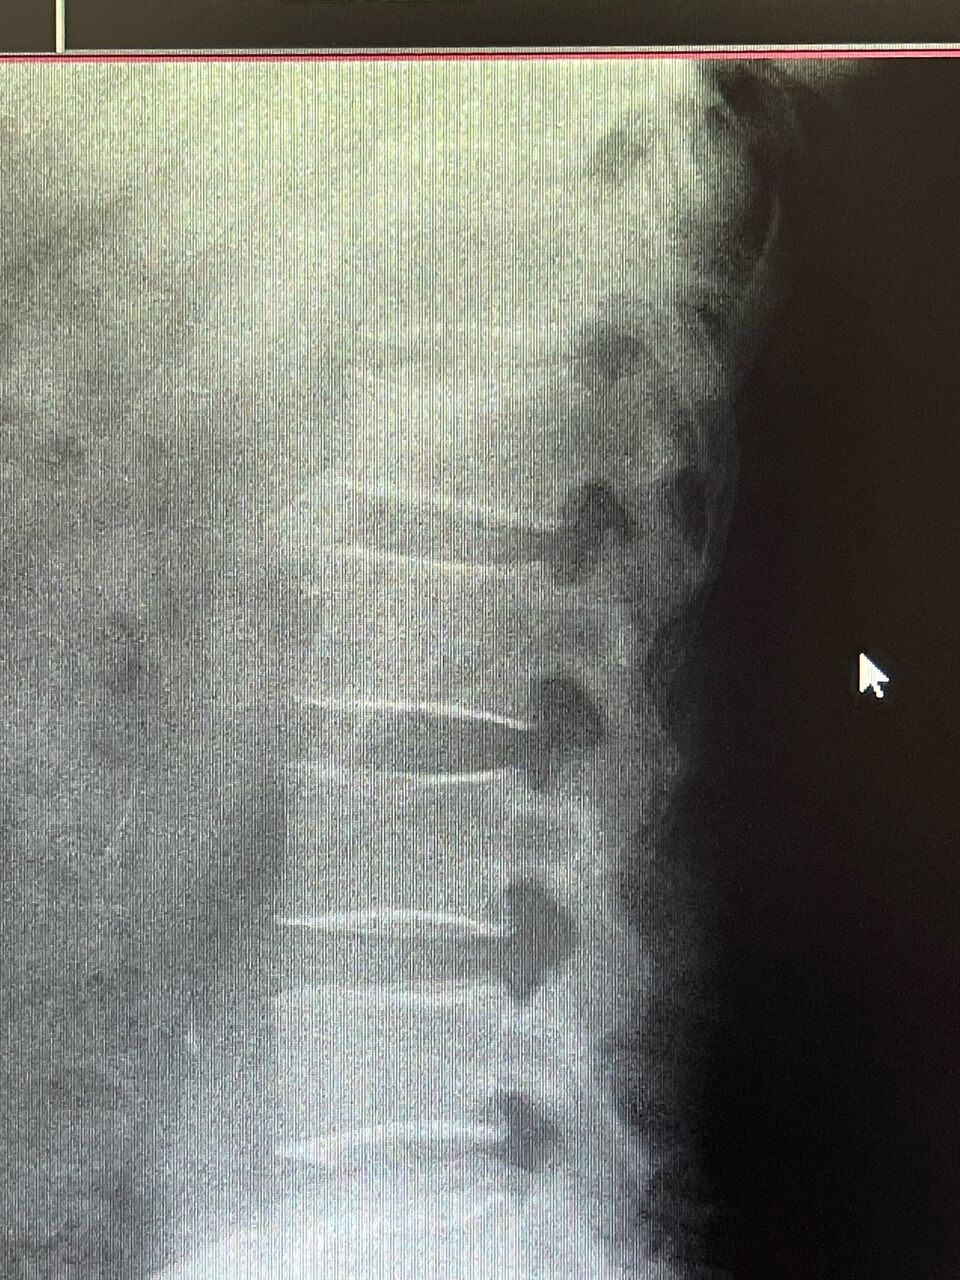

病名は、第一腰椎圧迫骨折。

下から5つ目の骨が潰れているのがわかりますか??

圧迫骨折は程度が酷いと手術が必要になる場合があります。

レントゲンを撮影するまではその判断ができないので非常に不安でした。

翌日病院でレントゲンを撮影して、状況を把握。 なんとかコルセットで治療ができそうなレベルだったので安心しました。(専門分野ですので、自分で診断、自分で治療をしています)